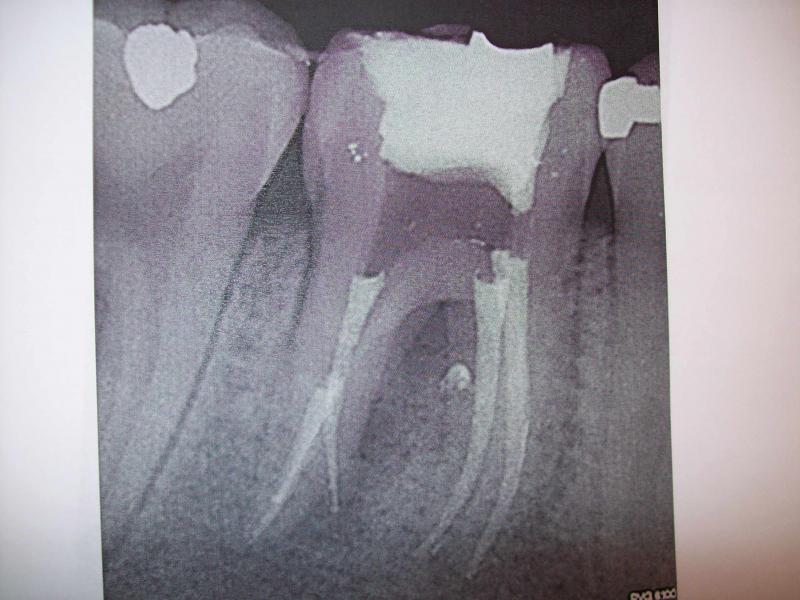

DR JET LOVES ROOT CANALS

General Dentist, Performs Root Canals ONLY - Microscope Trained Dentist

"DR. JET'S MISSION IS TO PERFORM ROOT CANALS FOR A REDUCED FEE USING THE LATEST TECHNOLOGY AND TECHNIQUES TO SERVICE THE MANY PEOPLE WHO ARE UNINSURED OR UNDER-INSURED GIVING EVERYONE AN OPPORTUNITY TO SAVE THEIR TOOTH!"